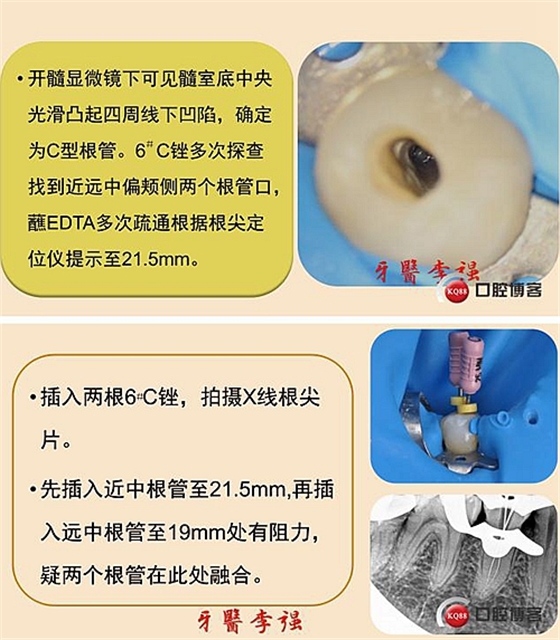

首頁(yè)牙體牙髓 第二前磨牙重度牛牙癥伴C型根管病例 科貿(mào)嘉友收錄

第二前磨牙重度牛牙癥伴C型根管病例 科貿(mào)嘉友收錄